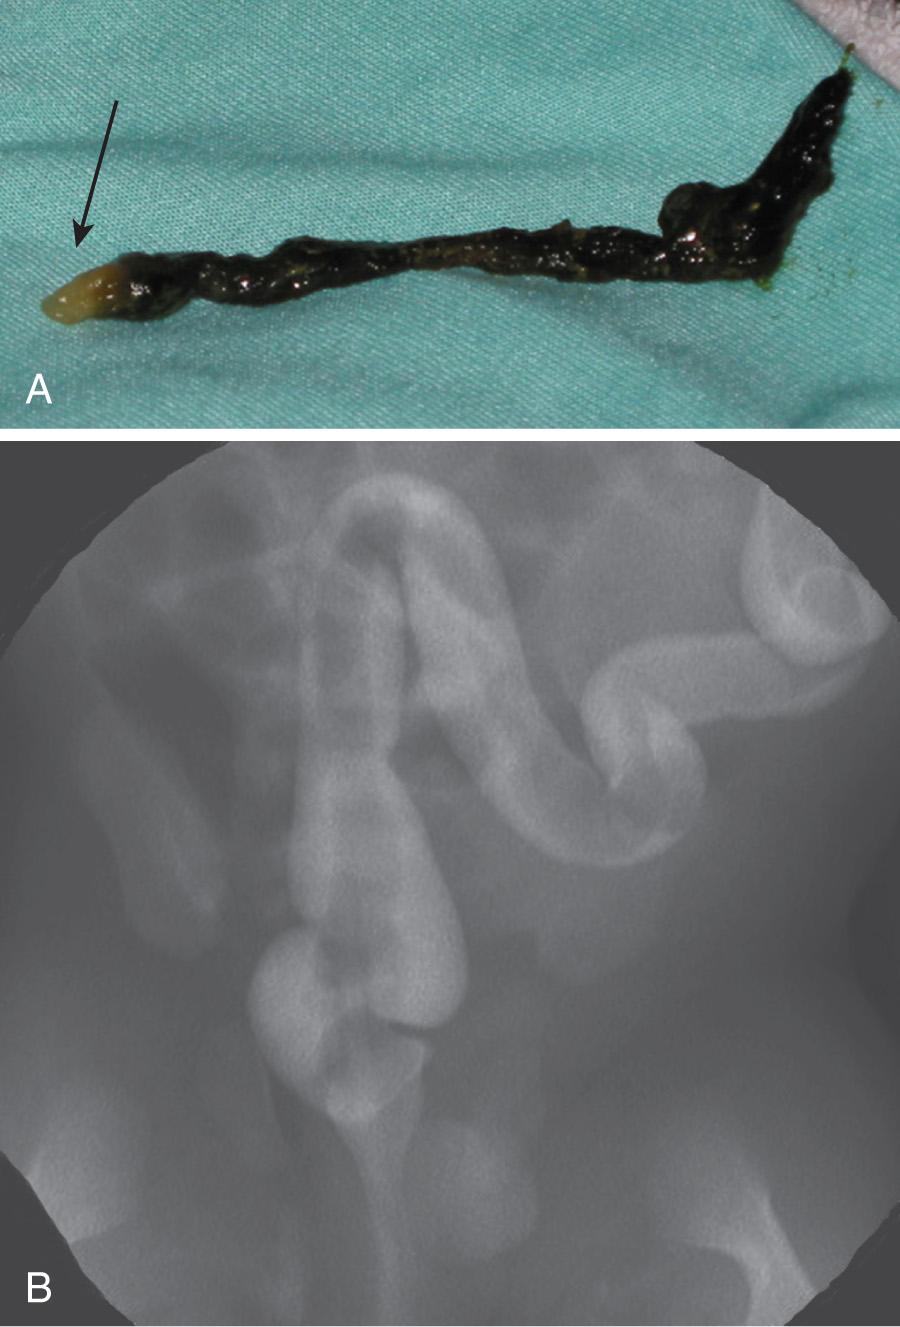

Treatment for simple meconium ileus is a high-osmolarity Gastrografin enema, as described for meconium plugs. If the procedure is unsuccessful or perforation of the bowel wall is suspected, a laparotomy is performed and the ileum opened at the point of largest diameter of the impaction. Approximately 50% of these infants have associated intestinal atresia, stenosis, or volvulus that requires surgery. The inspissated meconium is removed by gentle and patient irrigation with warm isotonic sodium chloride or N -acetylcysteine (Mucomyst) solution through a catheter passed between the impaction and the bowel wall. Some patients will require bowel resection with a temporary double-barrel enterostomy followed by serial irrigations and distal refeeding, or primary anastomosis at the initial operation. Most infants with meconium ileus survive the neonatal period. If meconium ileus is associated with CF, the long-term prognosis depends on the severity of the underlying disease (see Chapter 432 ).

Fig. 123.3, Uncomplicated meconium ileus.

Fig. 123.2, Meconium ileus.